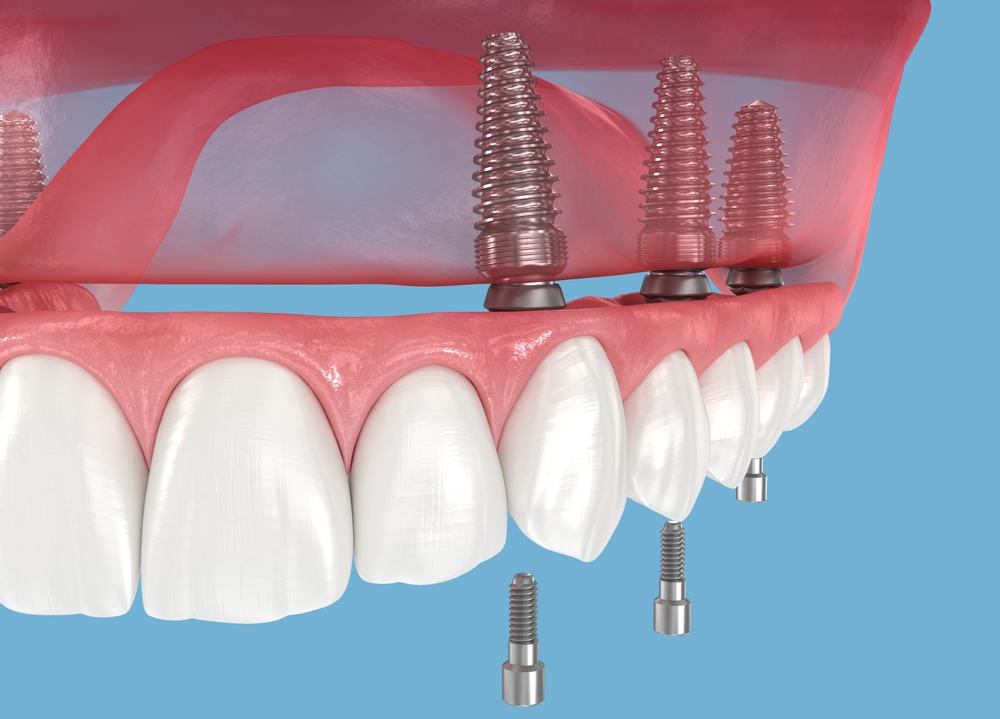

임플란트를 오래 사용하려면

집에서 실천할 수 있는

관리가 중요합니다.

식사 후에는 부드러운 칫솔을

사용해 천천히 닦아내고,

잇몸 가까운 부분은 세심하게

관리해주는 것이 좋습니다.

치실 또는 치간 전용 도구를 활용하면

임플란트 주변을 조금 더

깔끔하게 유지할 수 있습니다.

이렇게 꾸준히 관리하면 임플란트 염증이

생길 가능성을 줄이는 데

도움이 됩니다.

임플란트는 자연 치아보다 세정

사각지대가 생기기

쉬운 구조이기 때문에,

평소보다 한 단계 더 신경

쓰는 관리가 필요해요.